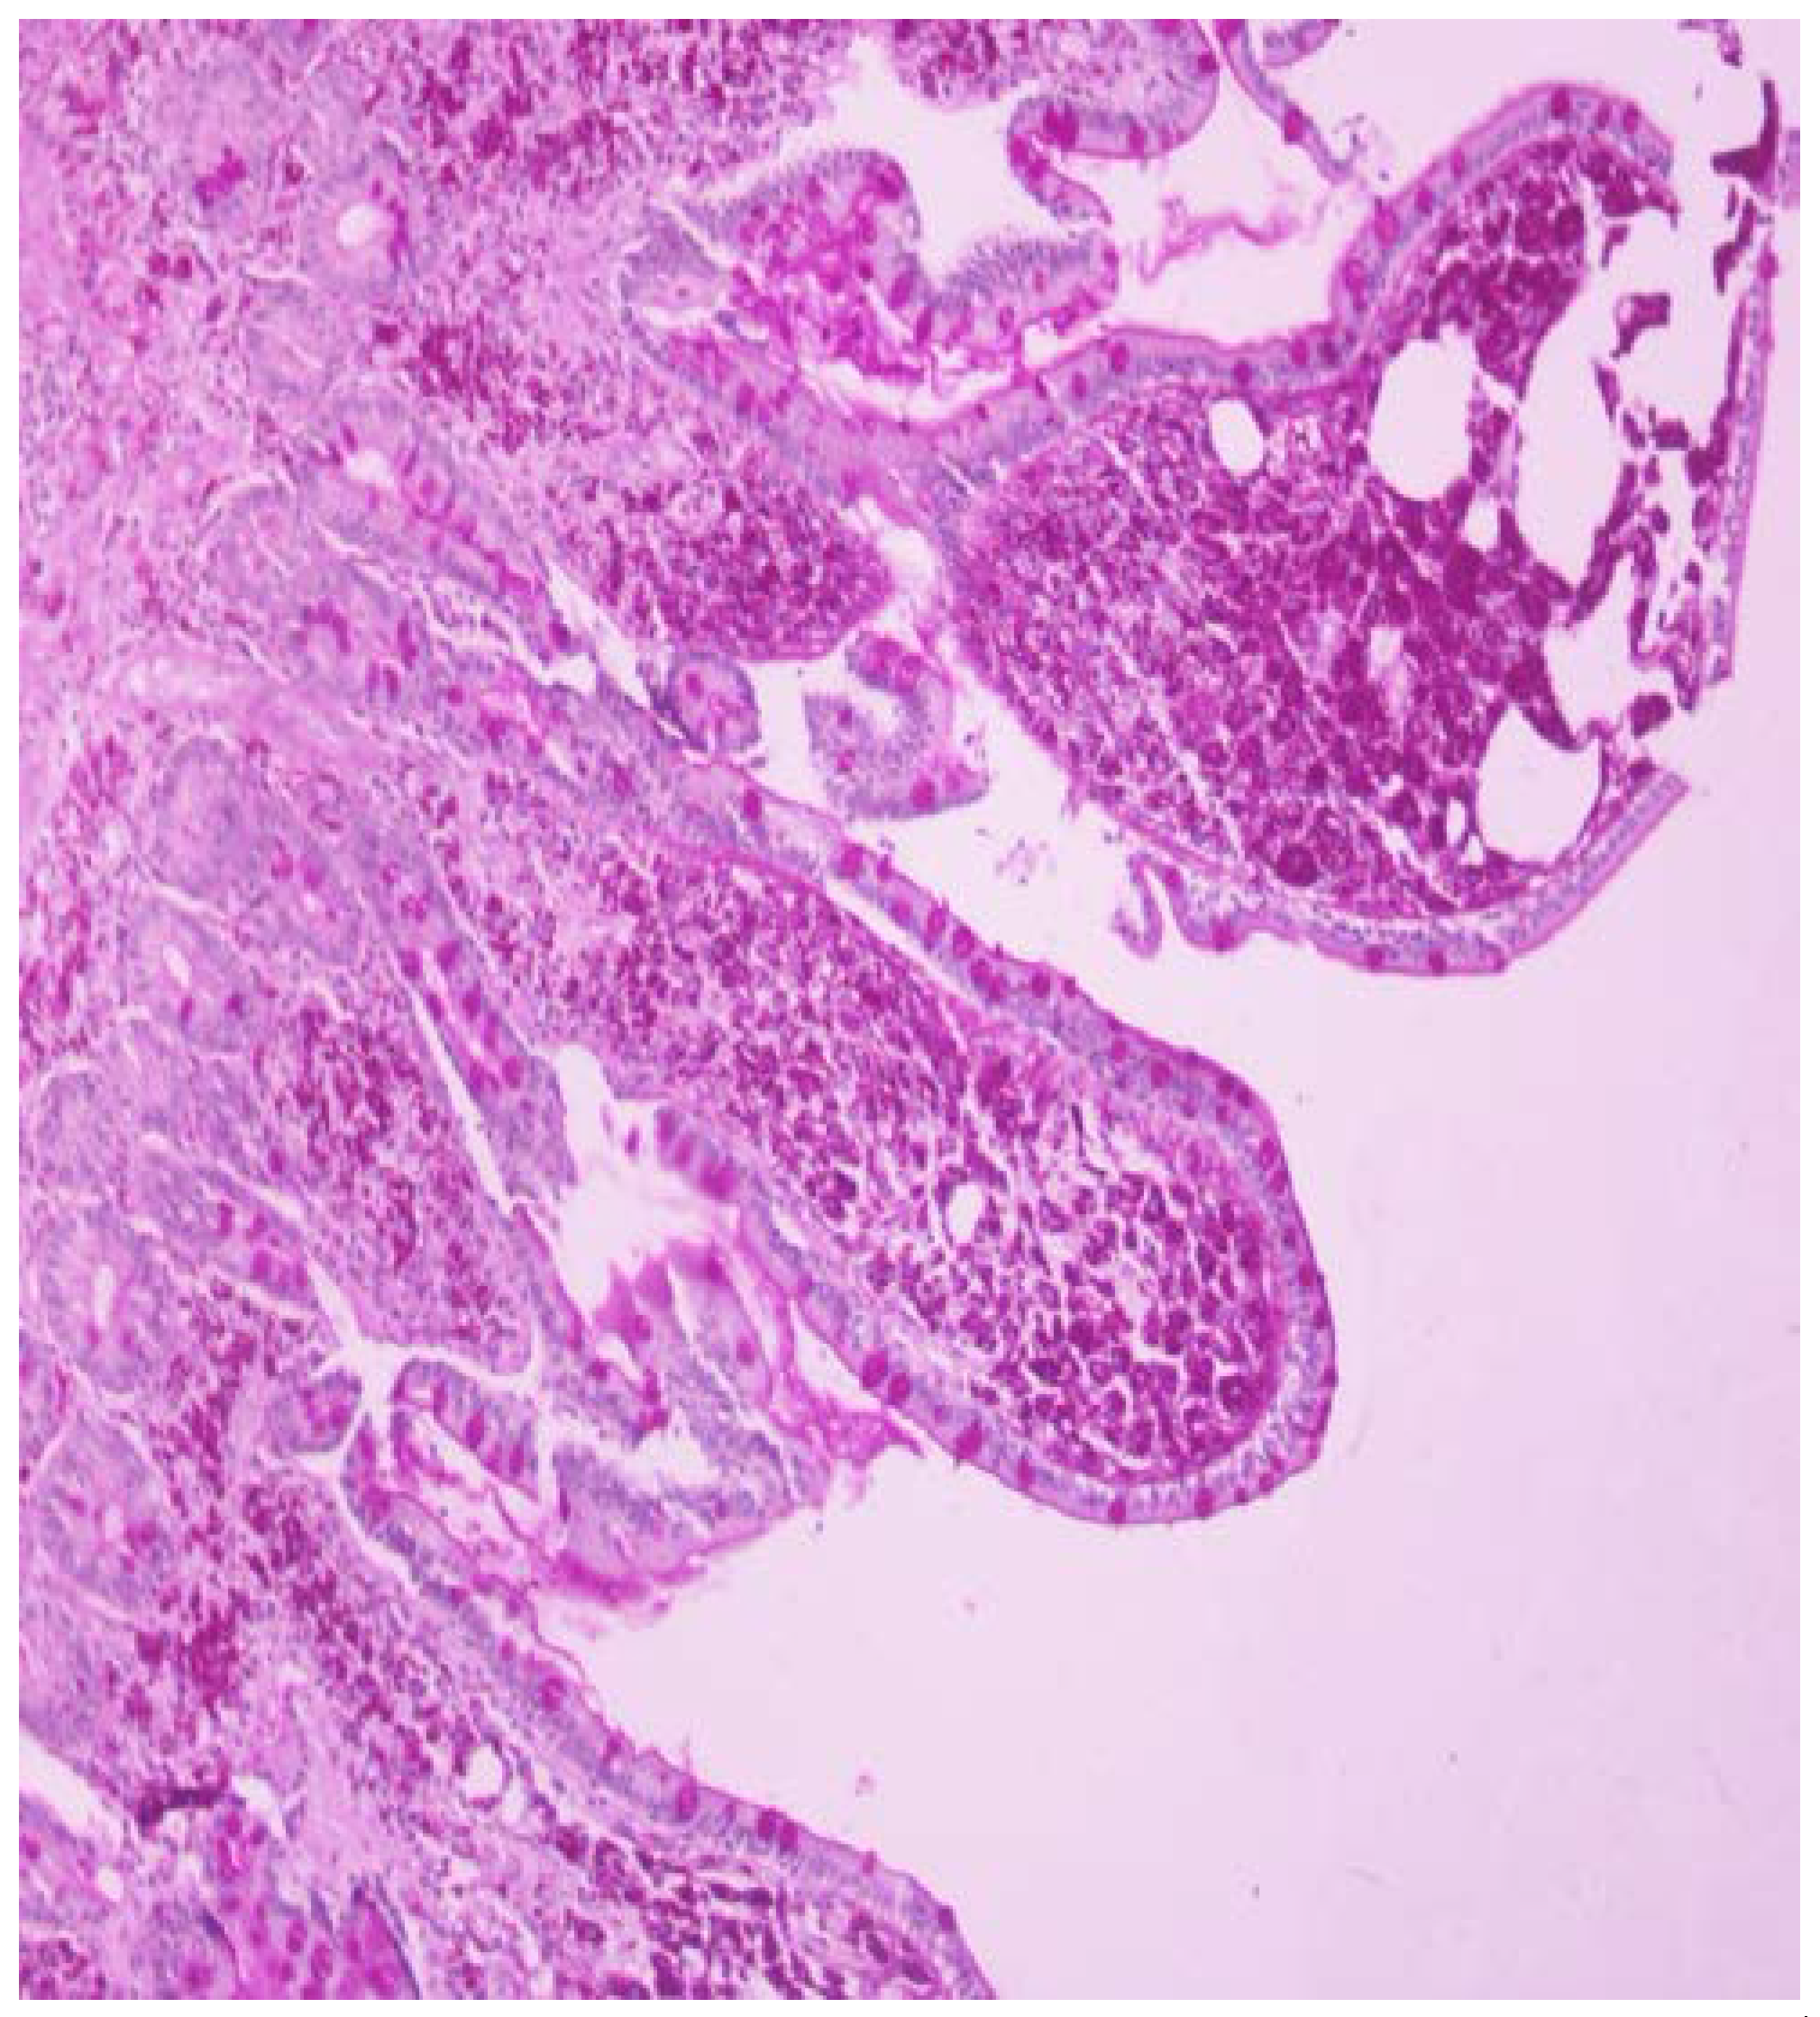

One month before admission the patient was referred to our endoscopy department due to chronic diarrhea and weight loss as an outpatient and she underwent gastroscopy with 2nd portion of the duodenum biopsies. One week before admission she was seen by her physician in the local hospital for low grade fever, weight loss and chronic diarrhea and she was referred to this hospital. Based on the initial history and findings a malabsorption syndrome was suspected. The slides were stained with hematoxylin and eosin (HE) and PAS and the biopsies revealed flattened villi, dense infiltrate of foamy macrophages with frequent PAS-positive bacilli within them, so Whipple’s disease diagnosis was suspected (Figure 1 and Figure 2).

Figure 1. Biopsy from the 2nd portion of the duodenum. The biopsy from the 2nd portion of the duodenum stained with hematoxylin and eosin (HE) and periodic acid– Schiff (PAS) showing reduction of villi and presence of lamina propria infiltrates with foamy macrophages containing (PAS)-positive, non-acid-fast granules.